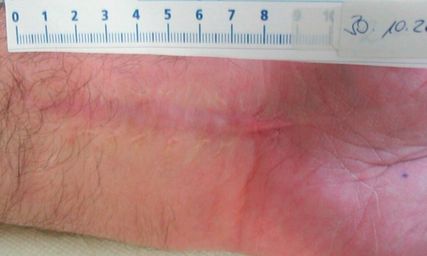

Abb. 1: Zustand nach palmarer Radiusverplattung mit hypertropher Narbe 11 Monate postoperativ

Pathologische Narben wie hypertrophe Narben und Keloide stellen eine häufige postoperative Komplikation dar. Während Therapien traditionell erst nach Manifestation einsetzen, zeigen aktuelle Daten, dass eine frühzeitige oder prophylaktische ESWT die Narbenmorphogenese günstig beeinflussen kann. In einer klinischen Pilotstudie zur Abdominoplastik führte bereits eine einmalige präoperative ESWT zu einer signifikanten Reduktion von Narbendicke und Gesamtnarbenbewertung (Vancouver Scar Scale). Auch bei bestehenden hypertrophen Narben wurden Verbesserungen in mehreren POSAS-Parametern beobachtet.Experimentelle und klinische Studien belegen, dass ESWT das Wundmilieu frühzeitig moduliert. Tiermodelle zeigen eine beschleunigte Reepithelialisierung, gesteigerte Angiogenese und verbesserte Gewebequalität. Klinisch konnten reduzierte Transplantationsraten und geringere Inzidenzen hypertropher Narben nachgewiesen werden. Randomisierte Studien berichten insbesondere eine verbesserte Narbenelastizität. Auf molekularer Ebene werden u. a. eine Hemmung der TGF-β 1/Smad-Achse sowie eine reduzierte Myofibroblastenaktivität beschrieben. Zudem beschleunigt ESWT die Epithelialisierung akuter Wunden und Transplantationsstellen, verkürzt die Heilungszeit, reduziert Wundfläche und Infektionsraten ohne relevante Nebenwirkungen. Auch bei chirurgischen Wunden wurden eine verbesserte Heilung und weniger antibiotische Therapien gezeigt. Zusammenfassend weist ESWT ein breites präventives Potenzial in der Modulation von Narbenbildung und Wundheilung auf und könnte in vielen chirurgischen Fächern eine wichtige Rolle in der Prävention von Wundheilungsstörungen spielen.